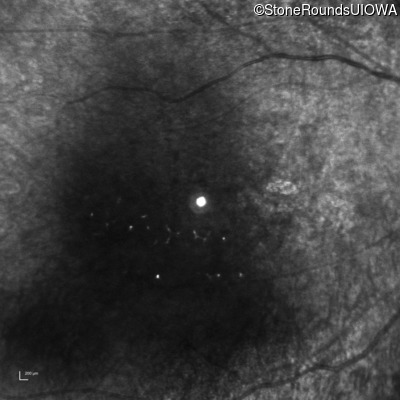

The clinical features supporting the diagnosis of Bardet Biedl syndrome in this patient include: bone-spicule-like pigmentation, narrowed arterioles and macular atrophy on ophthalmoscopy; photoreceptor loss on OCT; ulnar polydactyly, obesity, abnormal cognition, hypertension; and, normally sighted parents.